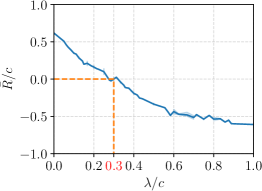

To gain deeper insights into the trade-offs related to the cost parameters and , and their impact on the outcomes, we investigated the relationship between the relative cost and the resulting RPP normalized over the hospital cost, . Specifically, we varied the hospital visit cost parameter, , across the range , while adjusting the MLAC, , within the set . The association is illustrated in Figure 4c. We observed that exhibited an inverse, non-linear relationship with the increasing of . In other words, decreasing was beneficial for the resulting RPP. Specifically, when the ratio declines to , it becomes the critical trade-off point at which our policy begins to yield positive RPPs. The raw experimental data behind Figure 4c is shown in Suppl. Table S2